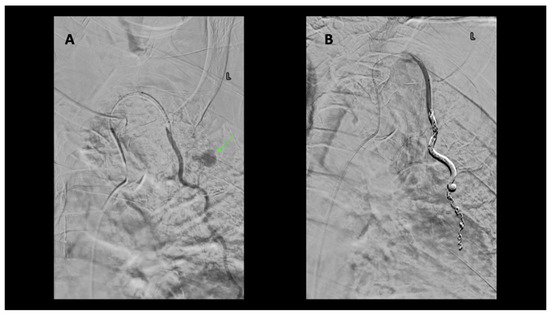

A 91-year-old-male with no significant past medical history presented following a motor vehicle accident. The patient, a rear seat restrained passenger, was involved in a front-end collision at 55 miles per hour. On admission, the patient complained of chest and abdominal pain. A seat belt shoulder strap injury was noted on the physical exam. In addition to a mediastinal hematoma, pulmonary contusion, sternal fracture, and multiple rib fractures, a CT scan of the chest showed active extravasation (Figure 1). Percutaneous intervention of the left internal mammary artery demonstrated a bilobed pseudoaneurysm arising from a LIMA side branch. Coil embolization was performed with the placement of detachable coils above, below, and across the origin of the side branch, the source of bleeding. Control percutaneous intervention after coil placement showed the cessation of extravasation and no further visualization of the pseudoaneurysm (Figure 2).

Figure 2. (A) Selective microcatheter digital subtraction angiogram (DSA) left internal mammary artery (LIMA) extravasation consistent with active bleeding/pseudoaneurysm from side branch of LIMA (white arrow). (B) Microcatheter DSA LIMA post coil embolization. Coils are deposited as a bridge covering the side branch bleeding source, sometimes referred to as sandwich technique or “jailing technique”, to eliminate antegrade as well as any retrograde or collateral flow to the bleeding side branch. No further extravasation. (C) Microcatheter “native” non-subtracted digital angiogram better demonstrates the occlusive coil pack.